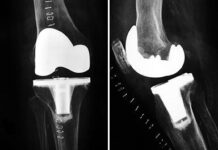

Vídeo de la Operación de Prótesis de Rodilla

El reemplazo total de la rodilla, o denominado médicamente, artroplastia de rodilla es una operación que se suele realizar a partir de los 60...